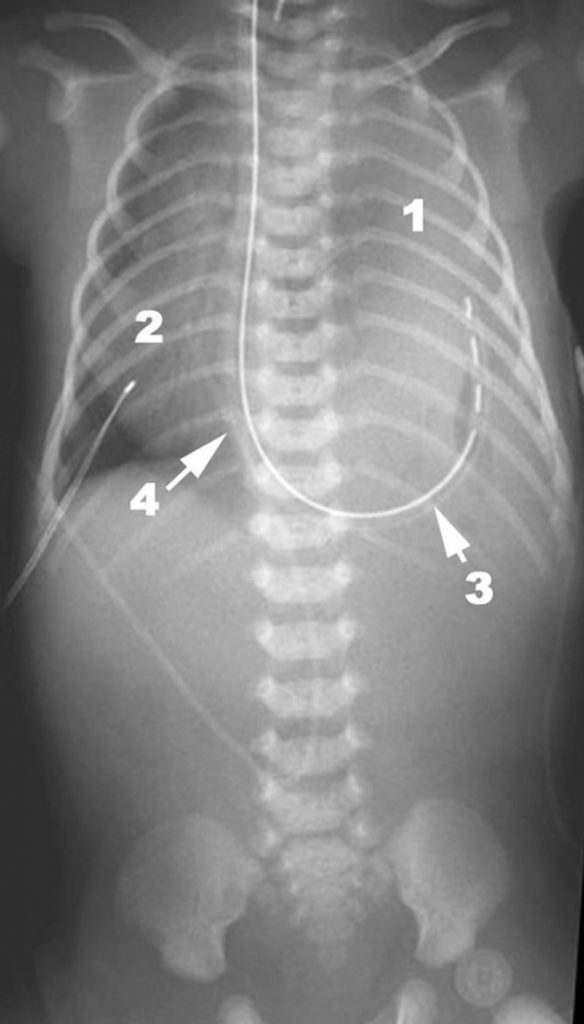

Les hernies diaphragmatiques sont le plus souvent localisées à gauche (figure 124.3), avec présence dans l’hémithorax gauche d’anses digestives et parfois de l’estomac. La radiographie montre, en fonction de l’aération des anses digestives : un hémithorax gauche opaque (anses non aérées) ou un hémithorax gauche avec des images aériques (anses aérées), une absence d’anses digestives aérées dans l’abdomen, une déviation du médiastin à droite, une absence de visualisation de la coupole diaphragmatique gauche, une sonde nasogastrique en position intrathoracique (estomac intrathoracique).

Fig. 124.3 Cliché thoracoabdominal de face couché : hernie diaphragmatique gauche.

Hémithorax gauche opaque (1), déviation du médiastin à droite (2), sonde nasogastrique intrathoracique (3), cathéter veineux ombilical dans la veine cave inférieure (4).

Source : CERF, CNEBMN, 2022.